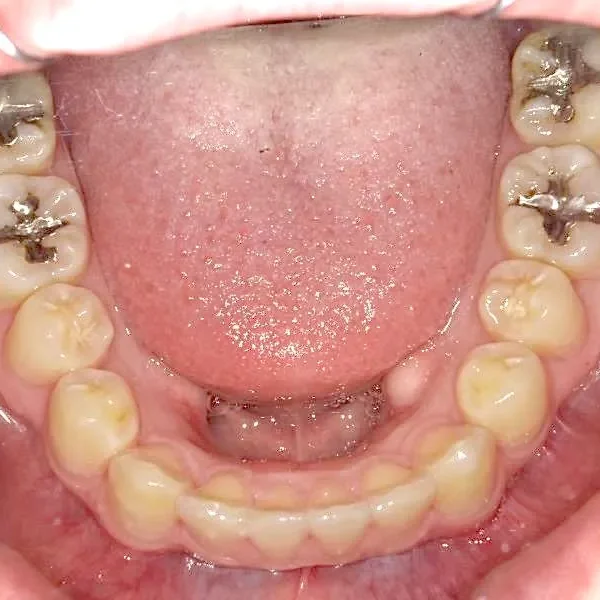

• 治療経過1

治療経過1

奥歯が内側と前方にかたむき上下の歯がガタガタに生えています。

90度ねじれた歯もあります。前歯も出っ歯になっています。

歯は抜かず、歯科矯正用アンカースクリューを用いて治療しました。

治療回数○回、2年9ヶ月の治療期間で矯正治療を終了しました。

主訴が改善され、ご満足頂きました。